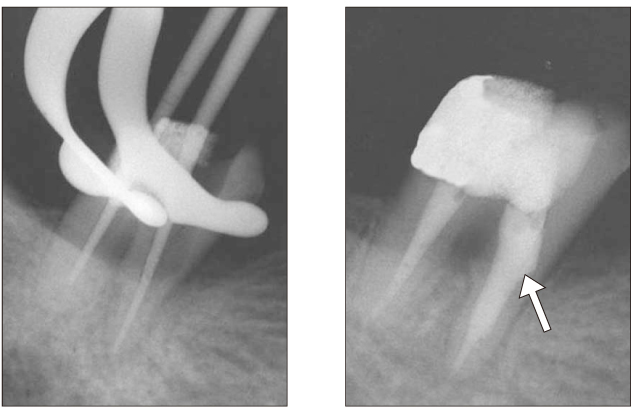

Figure 1

Diagnostic intraoral radiograph (a). Separated file in the mesial root isthmus (b, c) and remove it using ultrasonic device under microscope (d).

Figure 1 Diagnostic intraoral radiograph (a). Separated file in the mesial root isthmus (b, c) and remove it using ultrasonic device under microscope (d).